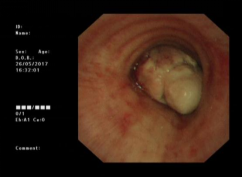

近年来,贵州航天医院各科室紧跟医学前沿,不断强技术、补短板,大力开展新技术、新项目,完成了许多高精尖、高难度、本地区“首例”的技术,填补了医院医疗技术空白,满足了群众日益增长的医疗需求。 贵州航天医院呼吸与危重症医学科是贵州省内呼吸疾病治疗规模最大,诊疗项目最全的呼吸疾病品牌科室,呼吸介入技术达到了全国先进水平,在贵州省内处于领先的地位。 本期,我们将为大家带来呼吸与危重症医学科特色技术——气道支架置入技术治疗呼吸不畅(已纳入乙类医保报销)。 案例分享 一患者因出现呼吸困难、气急等症状,听说我院呼吸与危重症医学科呼吸系统疾病诊疗实力在省内属于前列,慕名前来就诊,入院后,呼吸与危重症医学科为患者完善了胸部CT检查,提示:左主支气管肿瘤生长至气管下段,左肺不张,对此,科室立即组织多学科(MDT)讨论,对患者进行全面的诊断评估,诊断为:左肺鳞癌,左肺不张,气管下段内生型狭窄,左主支气管堵塞。 在充分了解患者及家属的治疗需求和征得治疗同意后,为进一步减轻患者呼吸困难症状,决定为患者实施气道支架置入技术,通过将支气管镜插入到气管中,使用气道球囊扩张器对狭窄的气道进行扩张,在病变部位置入支架扩张狭窄的支气管后,患者安全返回病房。 国产镍钛记忆合金支架植入步骤 术后,患者左主支气管通畅。 什么是气道支架置入技术 气道支架置入技术是一种用于治疗气道狭窄及气道相关性瘘等疾病重要的手段,尤其适用于因恶性肿瘤或其他原因导致的呼吸困难患者。是利用一种保持管腔完整性的人造装置——支架并应用支架置入器在X线透视或支气管镜直视下将支架置入气道保持气道通气功能的一种方法。 目前气道支架最常见的类型有可膨胀金属气道支架、硅酮支架及混合性支架等,以可膨胀金属支架为最常用。 气道支架置入技术原理 是将具有一定张力和弹力的支撑物(即气管支架)置入气道内,将狭窄或塌陷的气道撑开,从而维持气道通畅,或堵住破裂的瘘口。根据气管、支气管不同部位的解剖特点和病变情况,选择对应型号的支架,并通过气管镜的指引,在病灶位置植入合适的支架,也可根据气道的收缩性、不规则性和狭窄程度,进行适当调整。 气道支架置入技术优势 (一)快速缓解呼吸困难:支架置入能够迅速撑开狭窄或塌陷的气道,显著改善患者的呼吸困难症状。 (二)降低气道塌陷风险:对于某些肿瘤或炎症引起的气道狭窄,支架置入可以稳定气道结构,降低气道塌陷和窒息的风险。 (三)创伤小、恢复快:相较于传统手术,气道支架置入术具有微创的特点,患者术后恢复较快,痛苦较小。 气道支架可减轻或抵抗外部压力,扩大狭窄气道后,中央气道梗阻的症状和体征可立即减轻或消除,肺功能、运动能力及生活质量也得到改善。理想的气道支架应具备对气道壁物理性刺激小、置入后不移位、能阻止肿瘤或组织向支架内生长、不影响排痰、可以并容易回收等特点。 贵州航天医院 呼吸与危重症医学科专家团队 廖江荣 国务院政府特殊津贴专家 二级教授 主任医师 贵州航天医院副院长 国家级学术任职: 第二届中国医药教育协会介入微创专业委员会呼吸分会副主任委员 中国抗癌协会肿瘤微创治疗专业委员会常务委员 中国防痨协会结核病转化医学专业分会常务委员 第一届中国人体健康科技促进会呼吸介入专委会常务委员 中国医疗保健国际交流促进会结核病学分会第三届委员会常务委员 中国抗癌协会肿瘤微创治疗专业委员会粒子治疗学组第四届委员会委员 中华医学会结核临床专业委员会内镜介入委员 中华医学会放射学分会第十五届委员会介入学组呼吸系统介入专业委员会委员 北京健康促进会中青年专家委员会胸部疾病精准活检分委会副主任委员 中国医师协会介入医师分会第二届委员会肿瘤消融专业委员会委员 中国结核病防治综合质量控制专家指导委员会委员 亚洲冷冻治疗学会常务委员 世界内镜医师协会呼吸内镜协会常务理事 内镜临床诊疗质量评价专家委员会委员 “西部呼吸介入联盟”副理事长 专业擅长: 呼吸系统(肺)疑难病的诊断及危重病的抢救,呼吸系统(肺)感染性、疑难性疾病介入快速诊断(ROSE),尤其在肺癌、肺小结节早期诊断,肺癌微创综合靶向治疗,难治性、复治性、重症肺结核诊疗,硬质支气管下复杂性气道狭窄诊治,纤支镜介入治疗气道肿瘤、结核、气道狭窄(球囊扩张、支架植入、高频电刀、氩气刀、冷冻、灌洗、注药、微波消融),间质性肺疾病的诊疗上具有极高水平;带领团队勇于创新,在贵州省率先开展多项新技术、新疗法,如CT引导下及纤支镜下I125粒子植入及CT引导下微波、射频消融介入治疗肺癌等多项新技术,带动了贵州省肺部疾病的介入治疗水平提高。 蒋 婷 呼吸与危重症医学科 总负责人 副主任医师 专业擅长:从医20余年,在呼吸系统疾病、介入呼吸病学、肺部结核、肺部肿瘤等方面具有丰富的临床经验和专业技能,尤其是慢性阻塞性肺疾病、支气管扩张、肺结核、耐药肺结核、肺癌、胸腔积液等肺部疾病的诊治、微创介入、危重病患者抢救。 现任中国防痨协会人兽共患结核病专业分会委员,中国女医师协会第一届介入专业委员会委员,贵州省基层呼吸疾病防治联盟-间质性肺疾病联盟委员,贵州省防痨协会第七届理事会理事,贵州省中西医结合学会呼吸专业委员介入呼吸病学组委员,贵州省遵义市中医药学会中西医结合肺病(呼吸)分会副主任委员,贵州省遵义市中医药学会中医肿瘤专业委员会常委;发表论文数篇,参与并主持多项科研项目。 李桂凤 呼吸与危重症医学科 三病区 主任 副主任医师 专业擅长:从事呼吸系统疾病、结核病学、介入呼吸病学、肿瘤综合治疗、呼吸康复等临床工作20余年,擅长呼吸内科常见病、多发病及疑难重症危重病症的诊治,尤其对重症疑难结核及耐药结核病、介入治疗(肺)呼吸系统疾病、呼吸危重病抢救等方面具有较高诊疗水平。 中国防痨协会非结核病专业委员会委员,贵州省中西医结合学会第六届呼吸专业委员会委员,贵州省康复学会睡眠障碍康复专业委员会委员,遵义市呼吸内科医疗质量控制中心委员,遵义市落实民生实事结核病筛查阅片专家组成员;主持及参与实用新型专利3项。 周裕祥 呼吸与危重症医学科 四病区 主任 副主任医师 专业擅长:经皮肺介入、经血管介入诊疗技术。 贵州省中西医结合学会呼吸专业委员会介入呼吸病学组常务委员,中国医师协会呼吸医师分会介入呼吸病学工作委员会呼吸病血管介入学组委员,贵州省中西医结合学会呼吸学分会委员,遵义市医学会放射肿瘤治疗学分会委员,中国医药教育协会介入微创呼吸分会委员,北京健康促进会中青年专家委员会胸部疾病精准活检分委会委员;曾赴重庆医科大学RICU、珠海市人民医院介入科进修学习。 杨 芳 呼吸与危重症医学科 内镜中心 主任 副主任医师 专业擅长:从事临床工作约16年,对呼吸危重病的救治有独到的见解,尤其擅长呼吸系统疾病的介入诊疗,对呼吸内镜下的诊治及经皮肺穿刺诊疗技术具有丰富的临床经验。 亚洲冷冻治疗学会委员,中国医药教育协会介入微创呼吸分会委员,西南结核病医院联盟第二届委员会秘书/委员,贵州省中西医结合学会第六届呼吸科专业委员会委员,贵州省中西医结合学会呼吸专业委员会介入呼吸病学组秘书,贵州省中西医结合学会呼吸专业委员会基层康复学组副组长,贵州水利电力医学科学技术会高原医学分会委员,遵义市中医院学会中西医结合肺病(呼吸)分会秘书/常务委员,遵义市医学会肿瘤学分会(第二届)委员,遵义市医学会放射肿瘤治疗学分会第二届委员;主持及参与科研课题多项,参编著作《呼吸内镜操作技术规范》、《介入结核病学》,发表论文数篇。 贵州航天医院 呼吸与危重症医学科专家团队 贵州航天医院呼吸与危重症医学科以呼吸危重症和介入呼吸病学为强力推手,以肺部感染性疾病及肺癌、肺小结节的早期精准诊疗、慢性呼吸疾病康复治疗为特色,以人才团队建设为核心的科室发展模式,现已成为省内呼吸疾病治疗规模最大,诊疗项目最全的呼吸疾病品牌科室。是贵州省医学重点学科、临床医学重点专科建设单位,遵义市首批呼吸重点学科、重点专科建设单位。是国家卫健委能力建设和继续教育肿瘤微创介入建设中心、贵州省县级医院微创介入培训中心、遵义市呼吸疾病临床医学中心。是国家呼吸医疗质量控制与管理哨点医院、遵义市呼吸内科专业医疗质量控制中心。是中国医药教育协会介入微创呼吸分会呼吸介入技术培训中心单位;国家卫健委海医会呼吸分会ROSE专委会“诊断性介入肺脏病学快速现场评价”培训基地;中国肺癌防治联盟“贵州航天医院肺结节诊治”分中心,中国人体健康科技促进会呼吸介入技术培训基地,贵州省中西医结合会呼吸学分会呼吸介入专委会主委单位。 基本情况 平均每年开展气管镜诊疗约4000例,经皮肺穿刺介入诊疗近千例,开展的项目包括经支气管镜(软、硬)下冷冻、氩气刀、高频电刀、球囊扩张、支架置入、超声内镜诊疗等气道介入诊疗技术,经皮肺穿刺活检及肿瘤消融术(微波、冷冻)、ROSE技术、内科胸腔镜诊疗及经血管介入诊疗技术,且多项呼吸介入诊疗技术在省内处于领先水平。 诊疗范围 致力于呼吸系统感染性、疑难性疾病的介入快速精准诊疗;肺癌与肺小结节早期精准诊疗水平项目提升。擅长于呼吸系统(肺)疑难病的诊断及危重病的救治,尤其在肺癌、肺小结节的早期诊断;肺癌综合靶向治疗;肺结核综合诊疗;肺部疾病的介入诊疗在省内处于前沿水平。